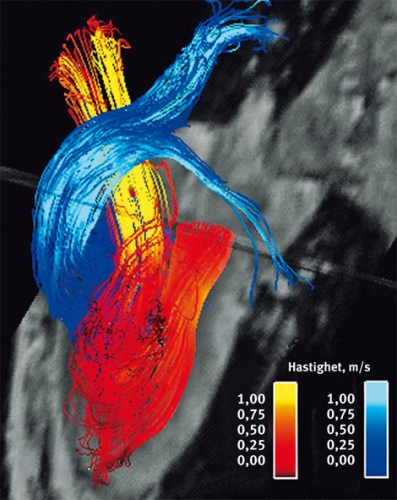

Blodflödets utsträckning i tid och rum kan beskrivas med hjälp av fyrdimensionell (3D + tid = 4D) faskontrast-MR [21, 22]. Resultatet av en mätning med 4D-faskontrast-MR är en tidsupplöst 3D-volym, där varje punkt i volymen representeras av en tidsupplöst hastighetsvektor, vilken beskriver hastighetens storlek och riktning. Den stora datamängden erbjuder en mångsidig analys men ställer även krav på kraftfulla analysverktyg. 4D-flödesdata ger underlag för att t ex påvisa blodelements väg över tid – s k partikelspår – eller momentana hastighetsfält vid olika tidpunkter i hjärtcykeln – s k strömlinjer [23, 24].

I vänster förmak ses ett välorganiserat flöde med en stor central virvel i systole, som upprätthåller bevarandet av rörelseenergi och säkerställer hög flödeshastighet också nära förmaksväggen [25]. Ett liknande välorganiserat flödesmönster har påvisats i vänster kammare [26] (Figur 2). Tidpunkten för flödets inträde i kammaren under fyllnadsfas påverkar flödets vidare väg. En del av flödet dröjer kvar i kammaren till efterföljande slag, och en annan del passerar ut i aorta under samma hjärtslag. Stora delar av det tidiga inflödet når hjärtspetsen, medan inflödet under förmakskontraktionen tar en kortare väg ut i aorta.

Blodflödet i aorta är komplext (Figur 3). Hastighetsprofilen i systole är asymmetrisk med högsta hastighet längs aortabågens innerkurva och inslag av skruvflöde. I diastole ses inslag av backflöde, även det med skruvprofil [32, 33]. Flödesmönstret i aortaroten, beskrivet med 4D-faskontrastteknik, har visat virvelstrukturer i sinus Valsalvae, något som postulerades redan av Leonardo da Vinci men som först nu har kunnat visas [27].